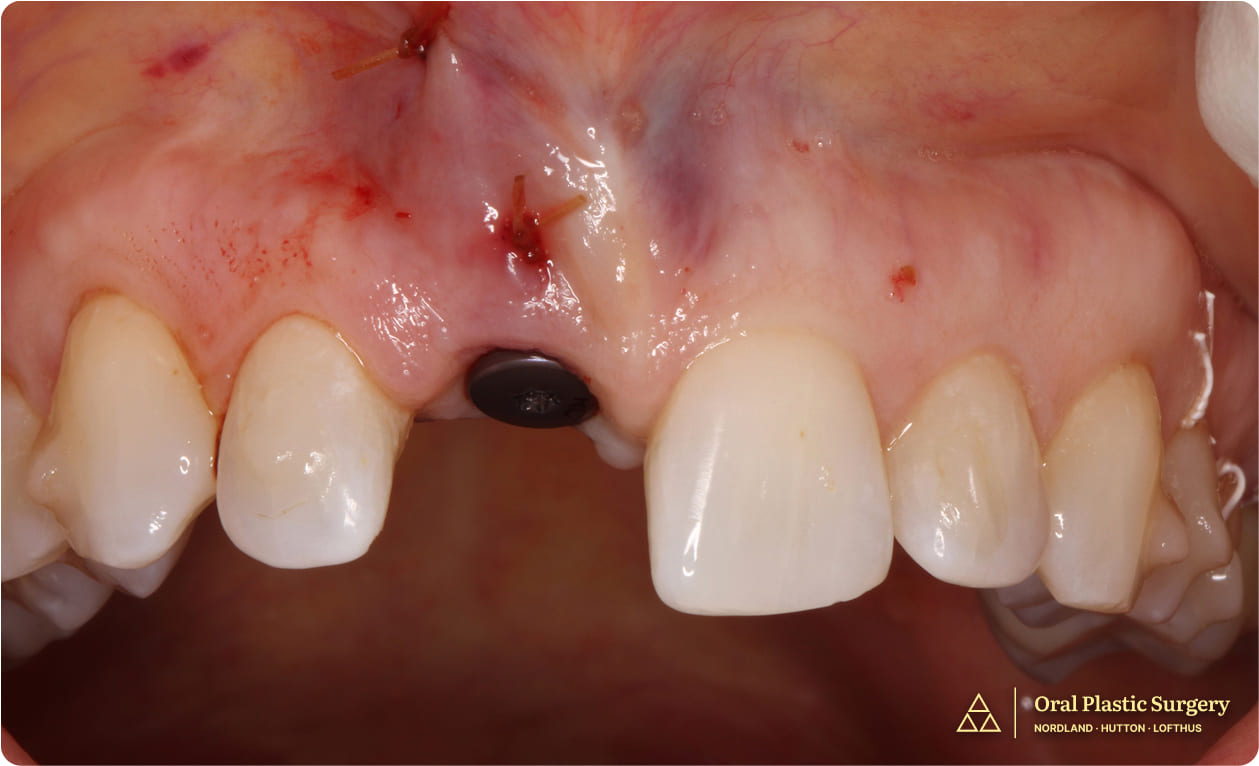

To begin, a 3D X-ray was taken to digitally map the site and guide the surgical plan. The fractured tooth was gently extracted, and an implant was placed immediately.

A free gingival graft was also performed at the time of extraction.

In place of donor or animal grafts, the patient’s own bone—harvested from a nearby tori—was used to support the implant.

A small blood sample was drawn and processed into a healing membrane called Leukocyte- and Platelet-Rich Fibrin (L-PRF), which was applied to enhance recovery.

The implant was uncovered, a healing abutment was placed, and a ridge augmentation was performed to improve the gingiva contour.